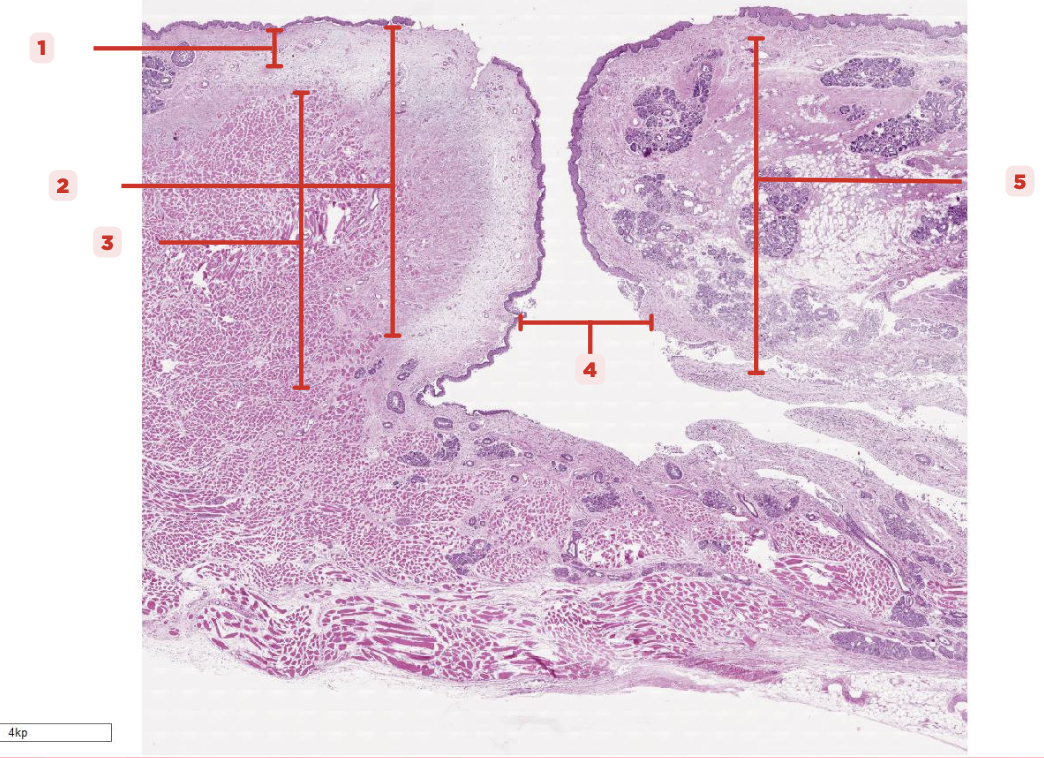

Identify the structure labeled as 1.

Laryngeal Ventricle

Space that separates the true and false vocal cords (#4)

True Vocal Cord

The #2 consists of a lamina propria that includes the vocalis ligament and a group of skeletal muscles known as the vocalis muscle.

Vocalis Ligament

Identify the structure labeled as 1.

True Vocal Cord

Identify the structure labeled as 2.

Vocalis Muscle

Identify the structure labeled as 3.

Laryngeal Ventricle

Identify the structure labeled as 4.

False Vocal Cord

Identify the structure labeled as 5.